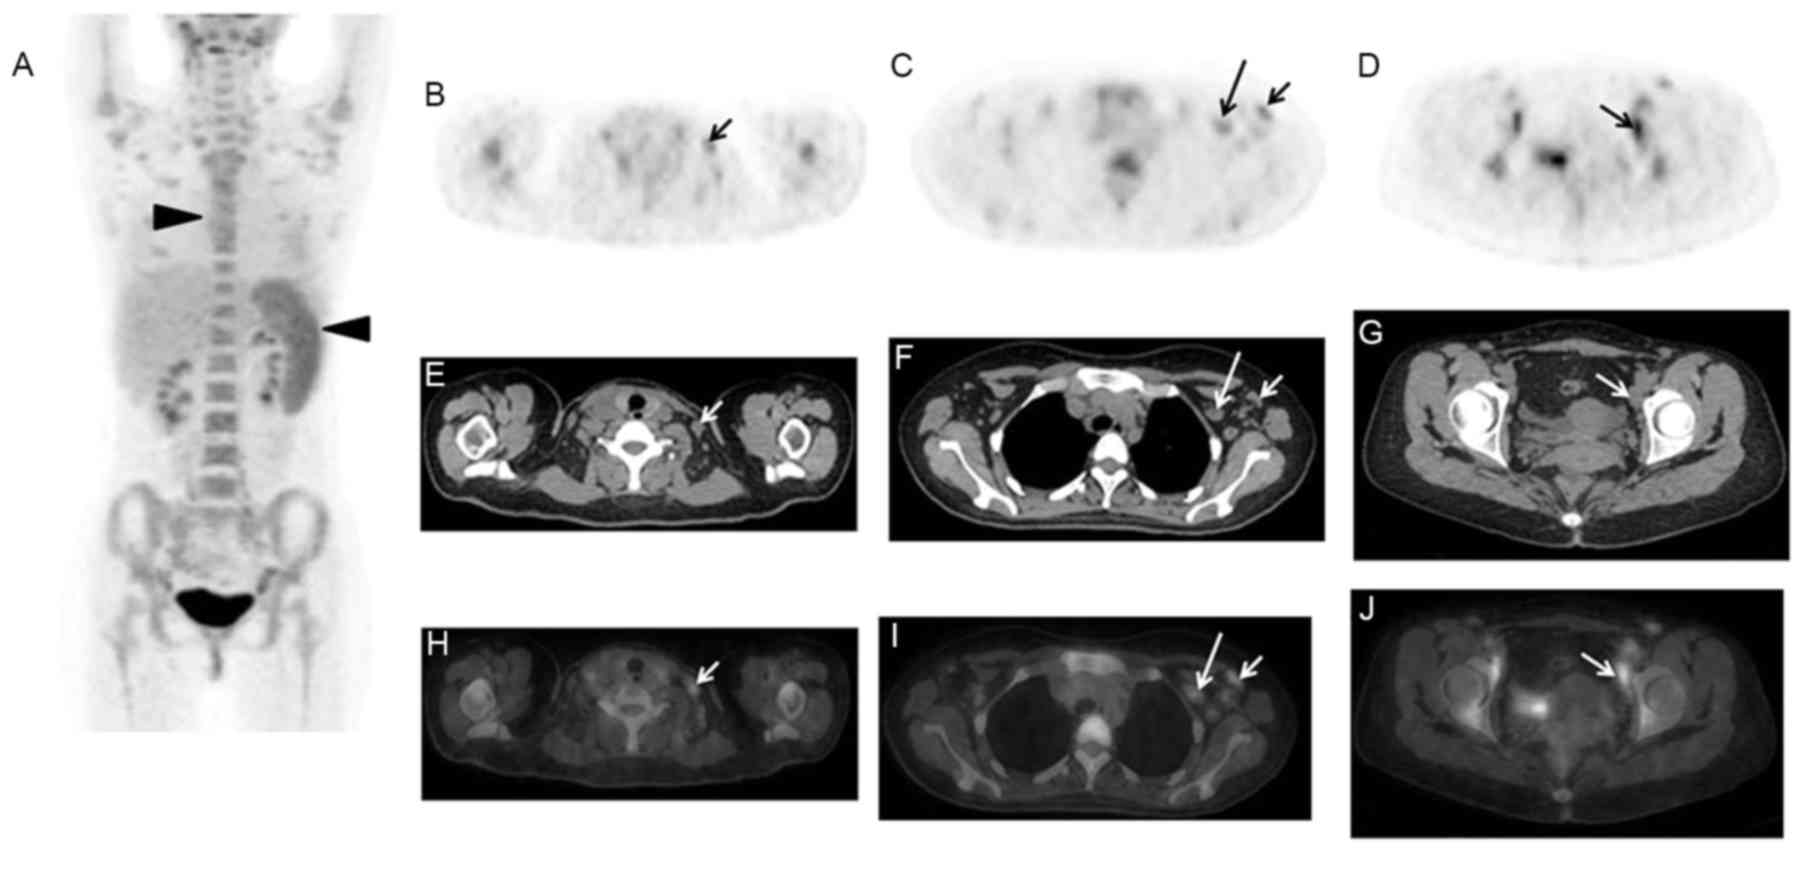

In addition, 1 case presented with marginally increased FDG uptake by the skin of the neck, shoulders and chest, which was caused by the skin rash of the corresponding part (Fig. 1). Another case displayed elevated FDG activity in the right shoulder joint, but the patient had no history of joint diseases. A total of 7 cases presented with effusion on the PET/CT images, including 4 cases with diffuse effusion (pleural, pericardial, abdominal and pelvic effusion; Fig. 2) and 3 cases with local effusion (2 patients with pericardial effusion and 1 patient with pelvic effusion). However, in the present study, no case of liver swelling and/or abnormal glucose metabolism was observed, and the mean SUVmax of the liver was 2.5±0.5 (range, 1.7–3.5).

Figure 2.

A 57-year-old male patient presented with fever (Tmax of 39.0°C) for 3 weeks, which was not relieved by anti-inflammatory therapy. 18F-FDG PET/CT imaging indicated that in addition to diffuse FDG uptake by the spleen and bone marrow (A: MIP, black arrows), bilateral pleural effusion with partial atelectasis was observed (B-D: PET, CT and PET/CT, white arrows). 18F-FDG, fluorodeoxyglucose; PET, positron emission tomography; CT, computerized tomography; MIP, maximum intensity projection.

Figure 3.

A 28-year-old male patient presented with fever (Tmax of 41.1°C) and joint pain for 1 month. 18F-FDG PET/CT imaging indicated only diffuse increases in FDG accumulation by bone marrow (A: MIP, arrows), of which the SUVmax was 2.8. In addition, marginal spleen swelling without abnormal FDG uptake was also observed (B-D: PET, CT and PET/CT). 18F-FDG, fluorodeoxyglucose; PET, positron emission tomography; CT, computerized tomography; MIP, maximum intensity projection; SUV, standardized uptake value.